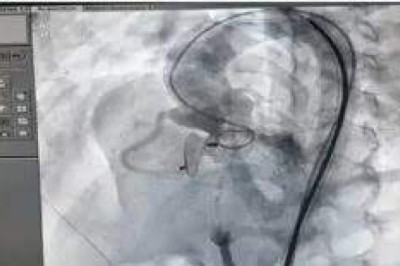

छत्तीसगढ़ में पहली बार ऐसी अनोखी हार्ट सर्जरी

त्वरित ख़बरें - :6 घंटे में दो बार ऑपरेशन;चीनी मिट्टी की तरह सख्त हो गया था दिल का बायां हिस्सा

छत्तीसगढ़ में दिल के मर्ज के इलाज में नए प्रयोग हो रहे

त्वरित ख़बरें -सरकारी डॉक्टरों ने जीरो एक्सेंट्रिक डिवाइस से दिल का क्रिटिकल छेद बंद किया